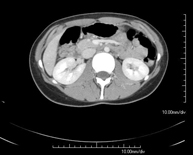

- Abdomen y pelvis- TC Abdomen Prueba diagnóstica que consiste en obtener imágenes del abdomen de alta definición anatómica (hígado, vesícula biliar, vía biliar, páncreas, bazo, estómago, intestinos, riñones, estructuras vasculares, vejiga, útero y ovarios, etc.) mediante el empleo de un equipo de TC (Tomografía Computarizada). Dichas imágenes se estudian posteriormente en una estación de trabajo que permite reconstrucciones bidimensionales en diferentes planos del espacio, y también reconstrucciones 3D (volumétricas). La mayoría de estudios requieren el empleo de contraste yodado para mejorar la definición de las imágenes. Prueba diagnóstica que consiste en obtener imágenes del abdomen de alta definición anatómica (hígado, vesícula biliar, vía biliar, páncreas, bazo, estómago, intestinos, riñones, estructuras vasculares, vejiga, útero y ovarios, etc.) mediante el empleo de un equipo de TC (Tomografía Computarizada). Dichas imágenes se estudian posteriormente en una estación de trabajo que permite reconstrucciones bidimensionales en diferentes planos del espacio, y también reconstrucciones 3D (volumétricas). La mayoría de estudios requieren el empleo de contraste yodado para mejorar la definición de las imágenes.

- TC Abdominopélvico Prueba diagnóstica que consiste en obtener imágenes bi y tridimensionales del abdomen y de la pelvis de alta definición anatómica (estructuras óseas, estructuras vasculares, hígado, páncreas, vesícula biliar, riñones, glándulas suprarrenales, bazo, intestino delgado y grueso, vejiga, útero y ovarios, próstata y vesículas seminales, uréteres, etc.) mediante el empleo de un equipo de TC (Tomografía Computarizada). La mayoría de estudios requieren el empleo de contraste yodado. Prueba diagnóstica que consiste en obtener imágenes bi y tridimensionales del abdomen y de la pelvis de alta definición anatómica (estructuras óseas, estructuras vasculares, hígado, páncreas, vesícula biliar, riñones, glándulas suprarrenales, bazo, intestino delgado y grueso, vejiga, útero y ovarios, próstata y vesículas seminales, uréteres, etc.) mediante el empleo de un equipo de TC (Tomografía Computarizada). La mayoría de estudios requieren el empleo de contraste yodado.